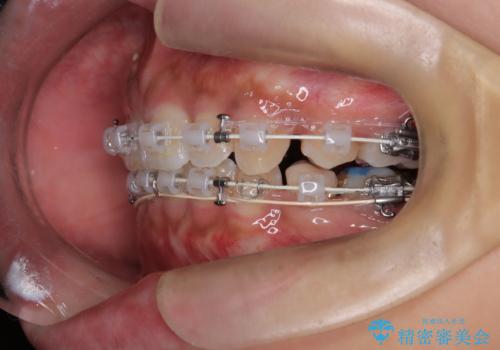

前歯の突出感を改善|上下4本の抜歯と審美ワイヤー矯正でバランスの取れた口元へ

- 患者様は、前歯の突出感を気にされて来院されました。診察の結果、歯列のスペースが不足しており、前歯を後方へ移動させるには抜歯が必要と判断。上下の小臼歯4本を抜歯し、目立ちにくい審美ワイヤー矯正(白いワイヤーと透明ブラケット)を使用して治療を行う計画を立てました。

抜歯によって前歯を下げるためのスペースを確保。その後、審美ワイヤー矯正を用いて、歯列全体のバランスを整えながら前歯を後方へ移動させました。治療後は、横顔のラインが整い、自然な口元になったことで、見た目も噛み合わせも改善しました。患者様からは「口元がすっきりして、自信を持って笑えるようになった」と喜びの声をいただきました。